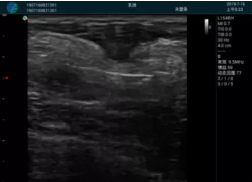

便攜超聲引導(dǎo)下人流術(shù)

病例一:

清晰顯示孕囊,通過軟件包計(jì)算孕齡7w+6d

M20實(shí)時(shí)引導(dǎo),術(shù)中清晰顯示孕囊被破壞和抽吸針的過程,清晰顯示吸引針

抽吸結(jié)束后縱切子宮,孕囊已被完全抽吸,未見明顯殘留

橫切子宮,發(fā)現(xiàn)右側(cè)宮腔靠近宮角處有少許脫模樣殘留

M20引導(dǎo)下,抽吸針找到右側(cè)宮角處再次清掃

二次抽吸后再次進(jìn)行超聲檢查,宮腔未見殘留,宮腔線清晰顯示

超聲引導(dǎo)下可視化人流是技術(shù)安全性的保障,一般對人流術(shù)設(shè)備預(yù)算不高,M20具備婦產(chǎn)科軟件包,且穿透力圖像質(zhì)量好,既滿足人流引導(dǎo)需要,也可用于床旁超聲的需求。